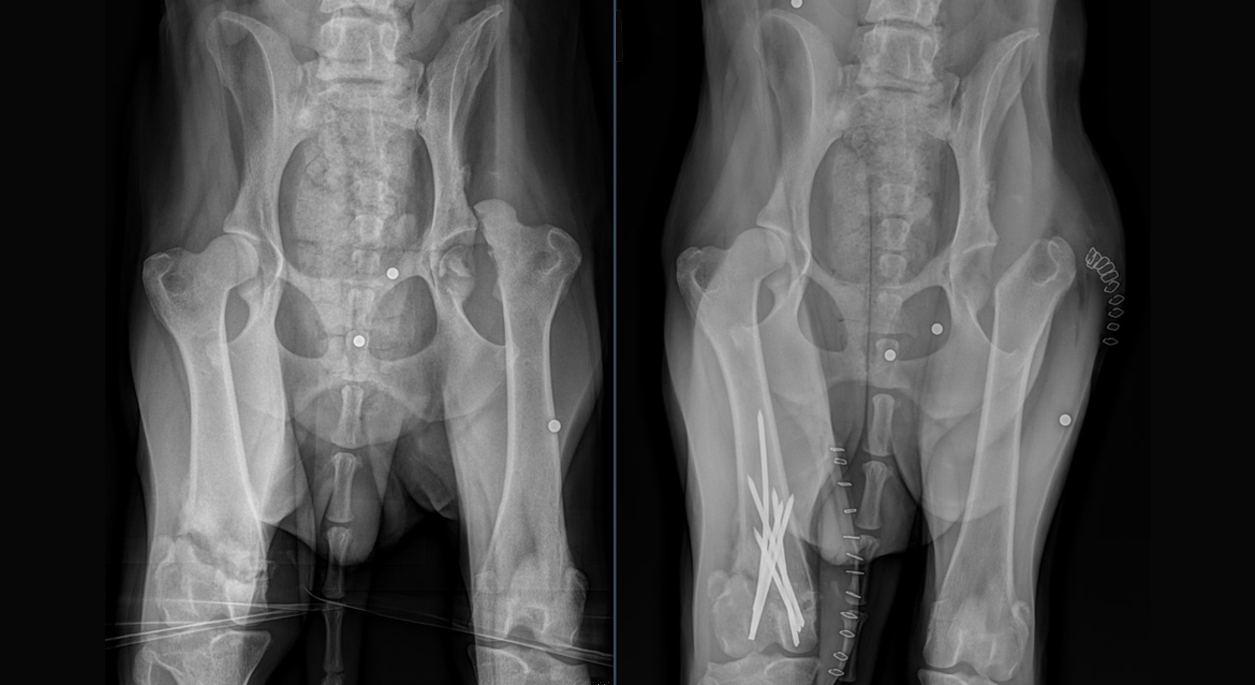

Sophie is an approximately 2 year old female Border Collie mix who was presented to the VSB Surgery Service with a 1.5 month history of bilateral pelvic limb lameness. The right pelvic limb lameness was historically significantly worse than the left. The lameness occurred due to an unknown trauma. Sophie was found with her injuries and no owner could be located. Sophie was initially retained by animal control before she was ultimately surrendered to a rescue organization, which then took over her care. Radiographs performed soon after her adoption demonstrated an intra-articular left femoral head fracture with coxofemoral luxation and an intra-articular right femoral trochlear fracture. Several ballistic projectiles were found scattered around the pelvis as well. There was no evidence of recent external puncture wounds, so the ballistic projectiles were presumed to have arrived during a previous traumatic event.

The bilateral nature of Sophie’s injuries made treatment recommendations difficult. A left femoral head and neck ostectomy was recommended for treatment of the left femoral head fracture and coxofemoral luxation. The treatment recommendation for the right femoral trochlear fracture was less clear. Amputation was considered, but fracture reduction and stabilization would likely result in a better overall function if such a procedure were possible. The relatively long time between injury and presentation raised concerns over the ability to alter the reduction and alignment of the bone fragments. Fibrosis and early bone healing could significantly inhibit attempts to alter the position of the bone fragments. After much consideration, the choice was made to proceed with left FHNO and right femoral trochlear fracture reduction and stabilization, if possible.